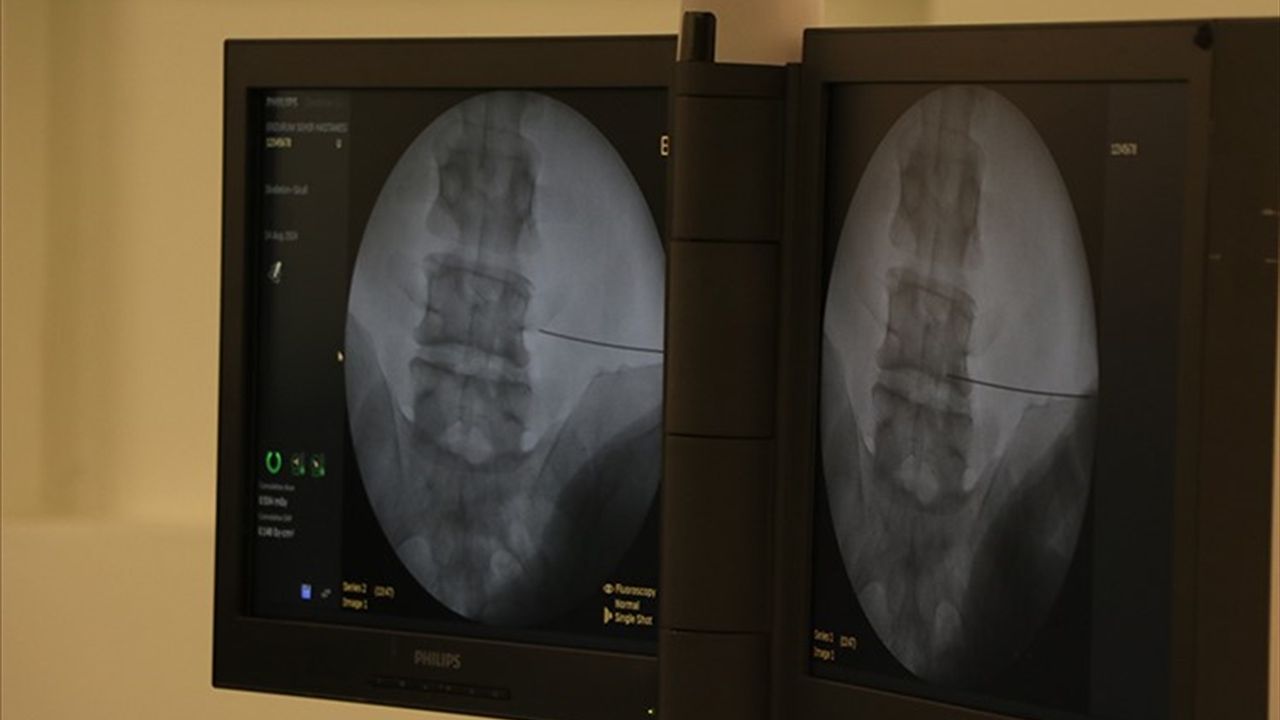

'Günümüzde fıtık ameliyatlarının açık ve laparoskopik (kapalı) yöntemlerle başarıyla uygulanıyor. Cerrahi yöntem hastaya özel olarak planlanıyor. Günümüzde fıtık ameliyatları son derece güvenlidir. Buna karşın fıtıkla uzun süre yaşamak ciddi riskler barındırır. Doğru bilgi, doğru zaman ve doğru tedavi hayat kurtarır.'